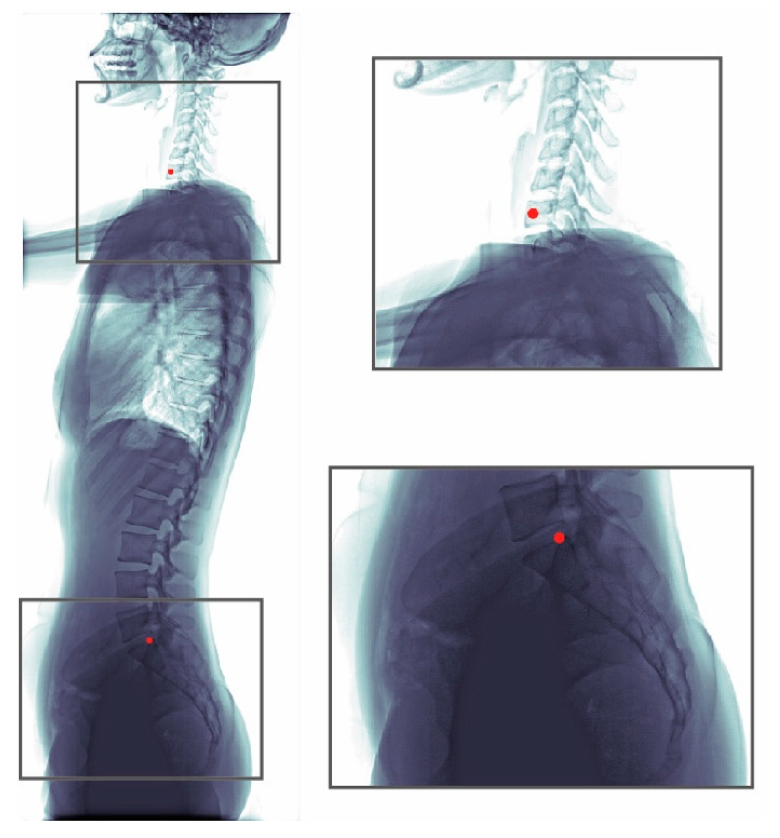

The whole dataset (990 images) was annotated by one senior resident orthopedic surgeon. This surgeon has more than five years of experience for manual measurement of spine parameters. When a difficult case was encountered, the surgeon discussed with an experienced spine surgeon to reach a consensus. This annotated dataset was used for model training and evaluation. An annotated radiograph can be seen in Figure 1. We used a custom written MATLAB GUI program for annotation.

Figure 1.

Annotations of a radiograph. The C7 center and the posterior corner of the sacrum were annotated (red dots).